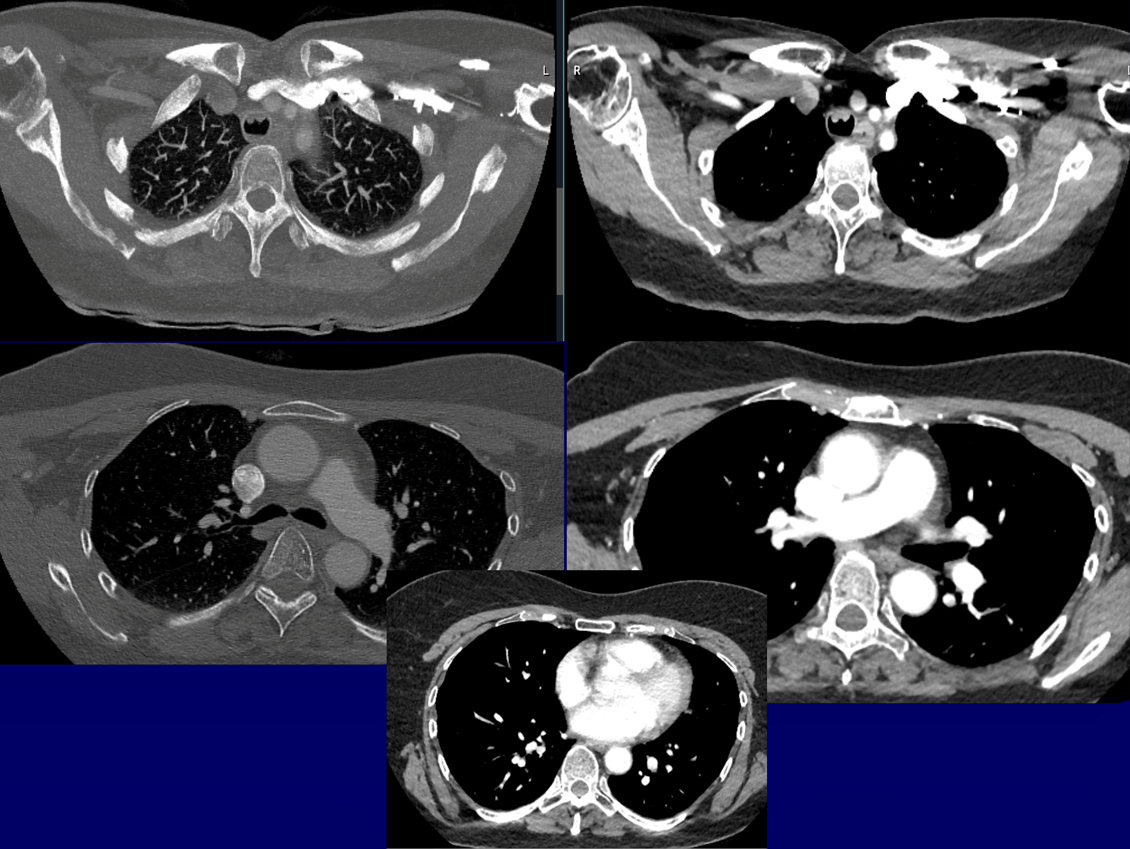

Patiente 29/12/1957 non fumeuse,

ATCD d’EOA T1N0M 1/3 ant corde vocale D TTT : IRX seule, Orthophonie OK

Bilan TDM de suivi à 2 ans, aucun signe fonctionnel clinique. Ex clinique normal.

QUEL EST VOTRE DIAGNOSTIC ?